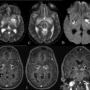

Multiple thin smooth ring enhancing lesions with central restriction in bilateral capsuloganglionic regions with perilesional edema and pachymeningeal enhancement in the left frontal and temporal regions

DD: pyogenic abscess with meningitis

Fungal etiology – cryptococcomas with meningitis ( immunocompromised state to be ruled out)

Cerebral toxoplasmosis

Neuro meliodosis